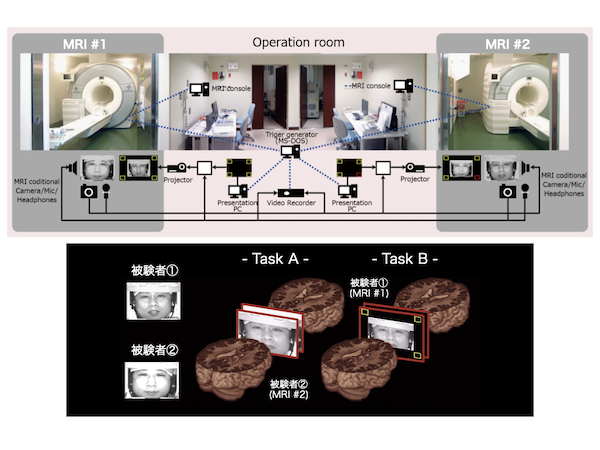

MRI自由自在 | 高原 太郎 |本 | 通販 | Amazon。商品詳細ページ | メディカルブックセンター。MRI応用自在−第4版 | 高原 太郎, 堀 正明, 本杉 宇太郎 |本。InSightec Japan株式会社 会社案内|お役立ち資料|INSIGHTEC。Victor Lift UpgradeでMRI検査室の 運用効率を最大化 ~3Tとの。とっつきにくいMRIのことをわかりやすく説明されている良書です。定藤 規弘 – 先端バイオイメージング支援プラットフォーム。ご理解いただけるかた、ご検討お願いします。Vantage Gracian が支える“先進的”な整形外科診療|東京先進整形。メジカルビュー社|書籍連動ダウンロードサービス。- タイトル: MRI 自由自在- 出版社: メディカルビュー社ご覧いただきありがとうございます。MRI応用自在−第4版 | 高原 太郎, 堀 正明, 本杉 宇太郎 |本。MRI応用自在−第4版 | 高原 太郎, 堀 正明, 本杉 宇太郎 |本。各ページにマーカー引いています。自宅保管なので、使用感あります。MRI応用自在−第4版 | 高原 太郎, 堀 正明, 本杉 宇太郎 |本。MRI検査 | 東京高輪病院 健康管理センター | 地域医療機能推進機構。